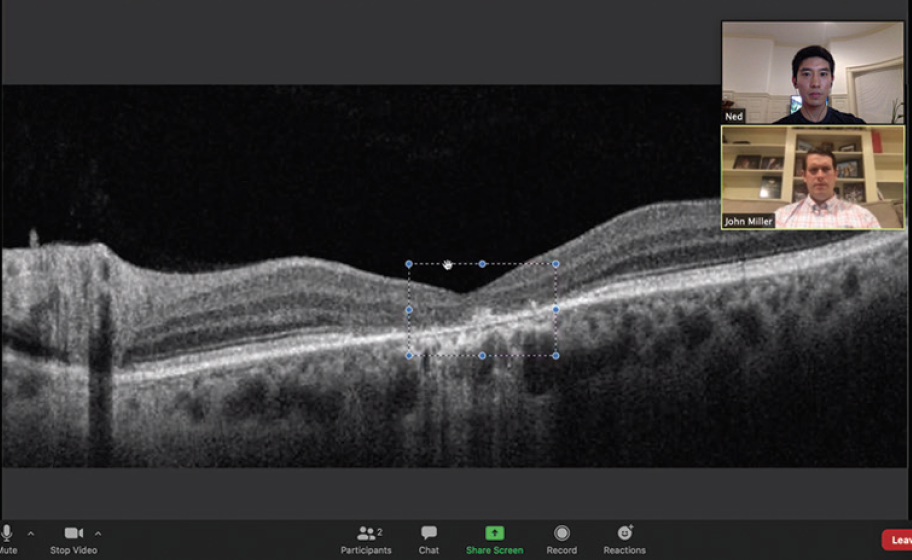

Figure. In a Zoom for Healthcare video call with a retina patient (in this example, the author Edward S. Lu, BA), the screen sharing feature allows display of an OCT image.

Improvements in videoconferencing platforms allow them to be used for high-quality virtual interactions between patients and providers. The general population’s increased exposure during the past decade to video-based communication with friends and family via platforms such as Facetime and Google Duo has made patients more accepting of video consultations. Zoom for Healthcare offers improved privacy (ie, multilayer security with AES-256 encryption), integration with Epic electronic health record (EHR) applications, and the ability to use enhanced collaboration features such as screen-sharing and annotations (Figure).6 Privacy in a health care setting remains paramount. One should note that Zoombombing, wherein unwanted third parties gain access to Zoom meetings, has occurred on the free version of Zoom.